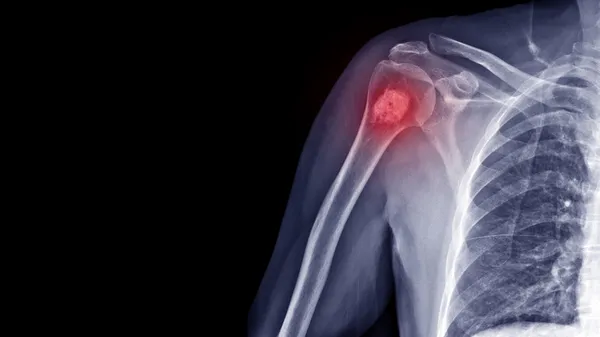

Tanı yöntemleri konusunda bilgi veren Dr. Öğr. Üyesi Savaş, en sık kullanılan yöntemin düz radyografi röntgeni sonrasında ise BT (Bilgisayarlı tomografi) ve MR (Manyetik rezonans) görüntüleme ile tanı konduğunu ifade etti.

Kötü huylu tümörlerin gidişatını belirlemek ve metastaz denilen yayılımını görmek amacıyla Pet-CT kullanıldığını anlatan Dr. Öğr. Üyesi Savaş, kesin tanının ise kemikten ya da yumuşak dokudan alınan biyopsi ile konulduğunu belirtti.